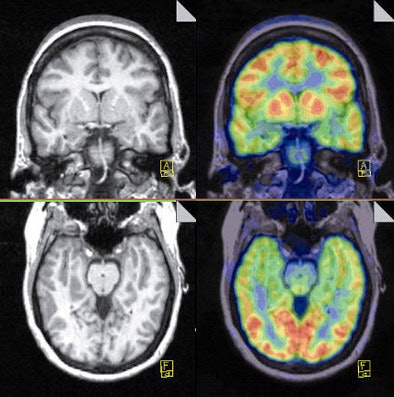

| A noncontrast T1-weighted MR image (left) shows fairly symmetric and moderate volume loss involving bilateral hippocampi, which illustrates a slight abnormal signal. The PET scan (right) is taken after an injection of 7.2 mCi FDG and shows symmetric FDG uptake in the cerebral cortex, subcortical gray matter, and cerebellum without definite focal area of hypometabolism. Image courtesy of Dr. Roland Talanow, the Cleveland Clinic. |